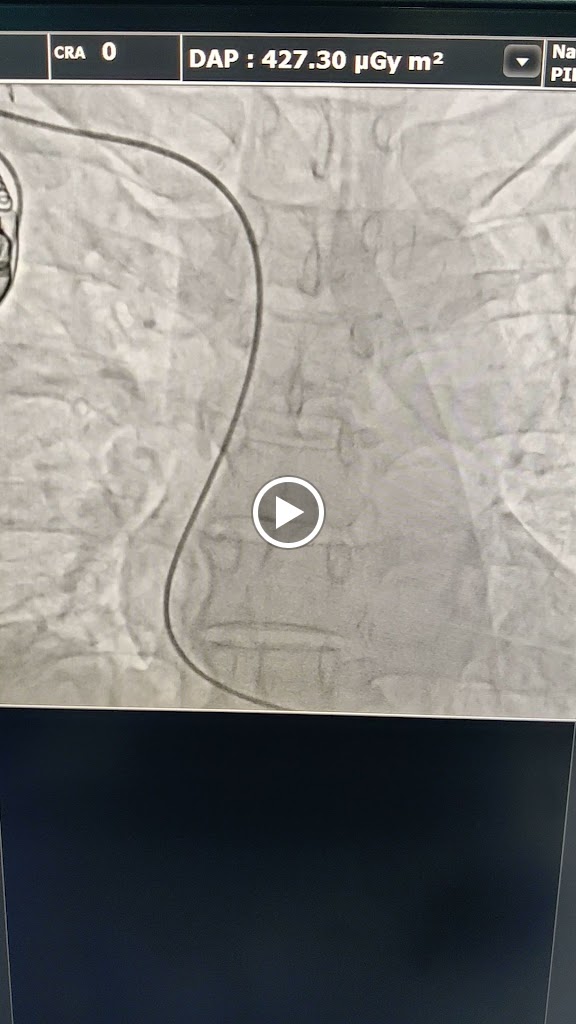

Myself Mukesh Kumar, a 41 yr old person had a severe cardiac arrest on 28th Oct'24 and attended by Dr Sumit Kumar Verma DM cardiology at Shanti Care Clinic, station road Begusarai Bihar. During angio it was observed that LAD 100% thrombotic occlusion from mid part & LCX mid part 99% thrombotic. In short, Double Vessel Coronary Artery Disease diagnosed successfully by Dr Sumit Kr Verma. I was almost dead. Not only me but also my whole family is very thankful to Dr Sumit Kumar Verma for saving my life. He is very professional, sincere, proactive and always available for his patients. He has done more than 100 cardio surgeries successfully.